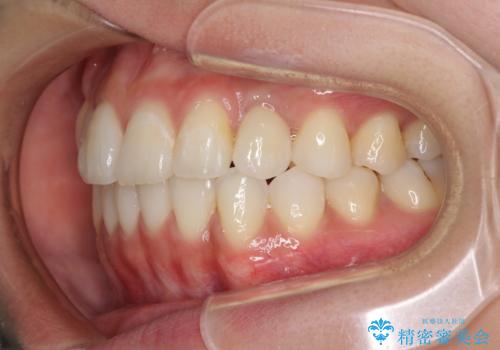

- 前歯のデコボコと残っている乳歯の部分へのインプラント治療を希望して来院された患者様です。

当初は目立たない上下裏側矯正を希望されていましたが、歯並びの悪さによる磨き残しが多く、歯肉炎が認められたため、より清潔な環境で治療を進められるインビザラインを選択することとしました。

前歯のデコボコが強かったため、上の奥歯を後方に動かす量が多くなり、結果として2年以上の治療期間を擁することとなりました。

歯並びが整ったことで治療前に認められた歯肉炎は全くなくなり、患者様には大変満足していただきました。